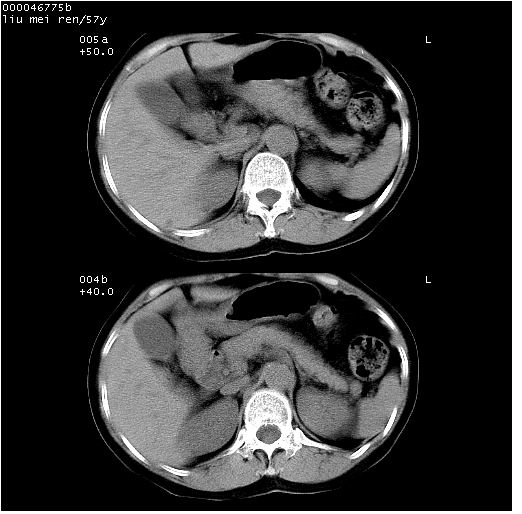

患者 女,57岁。因车祸受伤,其家属要求行“全身ct检查”。平素健康。

胸部ct轴位平扫(层厚10mm,螺距1.5,重建间隔10mm),图像如下: